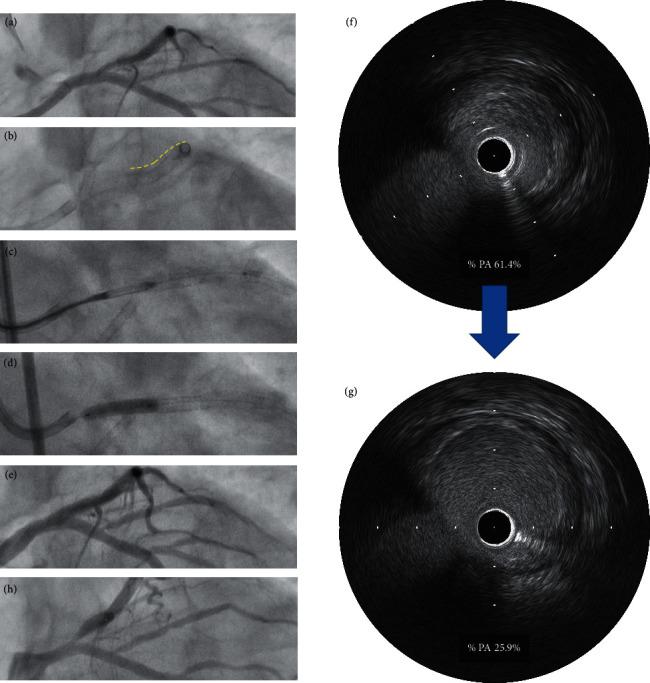

Among these 38 lesions, 31 lesions were de novo LM bifurcation lesions and 7 lesions were stent edge restenosis at the left anterior descending (LAD) ostium. The mean % plaque area (%PA) after DCA was 44.0 ± 7.4%. TVF at 12 months occurred in 1 lesion (3.2%) of de novo LM bifurcation lesion and in 3 lesions (42.9%) of stent edge restenosis at the LAD ostium. All events of TVF were ischemia-driven TLR by percutaneous coronary intervention. Among 4 TLR cases, %PA after DCA was high (55.9%) in the de novo LM bifurcation lesions; on the other hand, %PA after DCA was low (42.4%, 38.7%, and 25.7% in the 3 cases) in stent edge restenosis at the LAD ostium. No procedure-related major events were observed during hospitalization. There was no cardiac death, no myocardial infarction, no coronary artery bypass grafting, and no bleeding complications at 12 months.

在这 38 个病变中,31 个为新发 LM 分叉病变,7 个为左前降支(LAD)开口处支架边缘再狭窄。DCA 后的平均斑块面积百分比(%PA)为 44.0±7.4%。新发 LM 分叉病变的 1 个病变(3.2%)和 LAD 开口处支架边缘再狭窄的 3 个病变(42.9%)发生了 12 个月时的 TVF。所有 TVF 事件均为经皮冠状动脉介入治疗引起的缺血驱动 TLR。在 4 例 TLR 病例中,新发 LM 分叉病变的 DCA 后%PA 较高(55.9%);另一方面,LAD 开口处支架边缘再狭窄的 DCA 后%PA 较低(3 例分别为 42.4%、38.7%和 25.7%)。住院期间无操作相关的主要不良事件。12 个月时无心脏死亡、心肌梗死、冠状动脉旁路移植术和出血并发症。